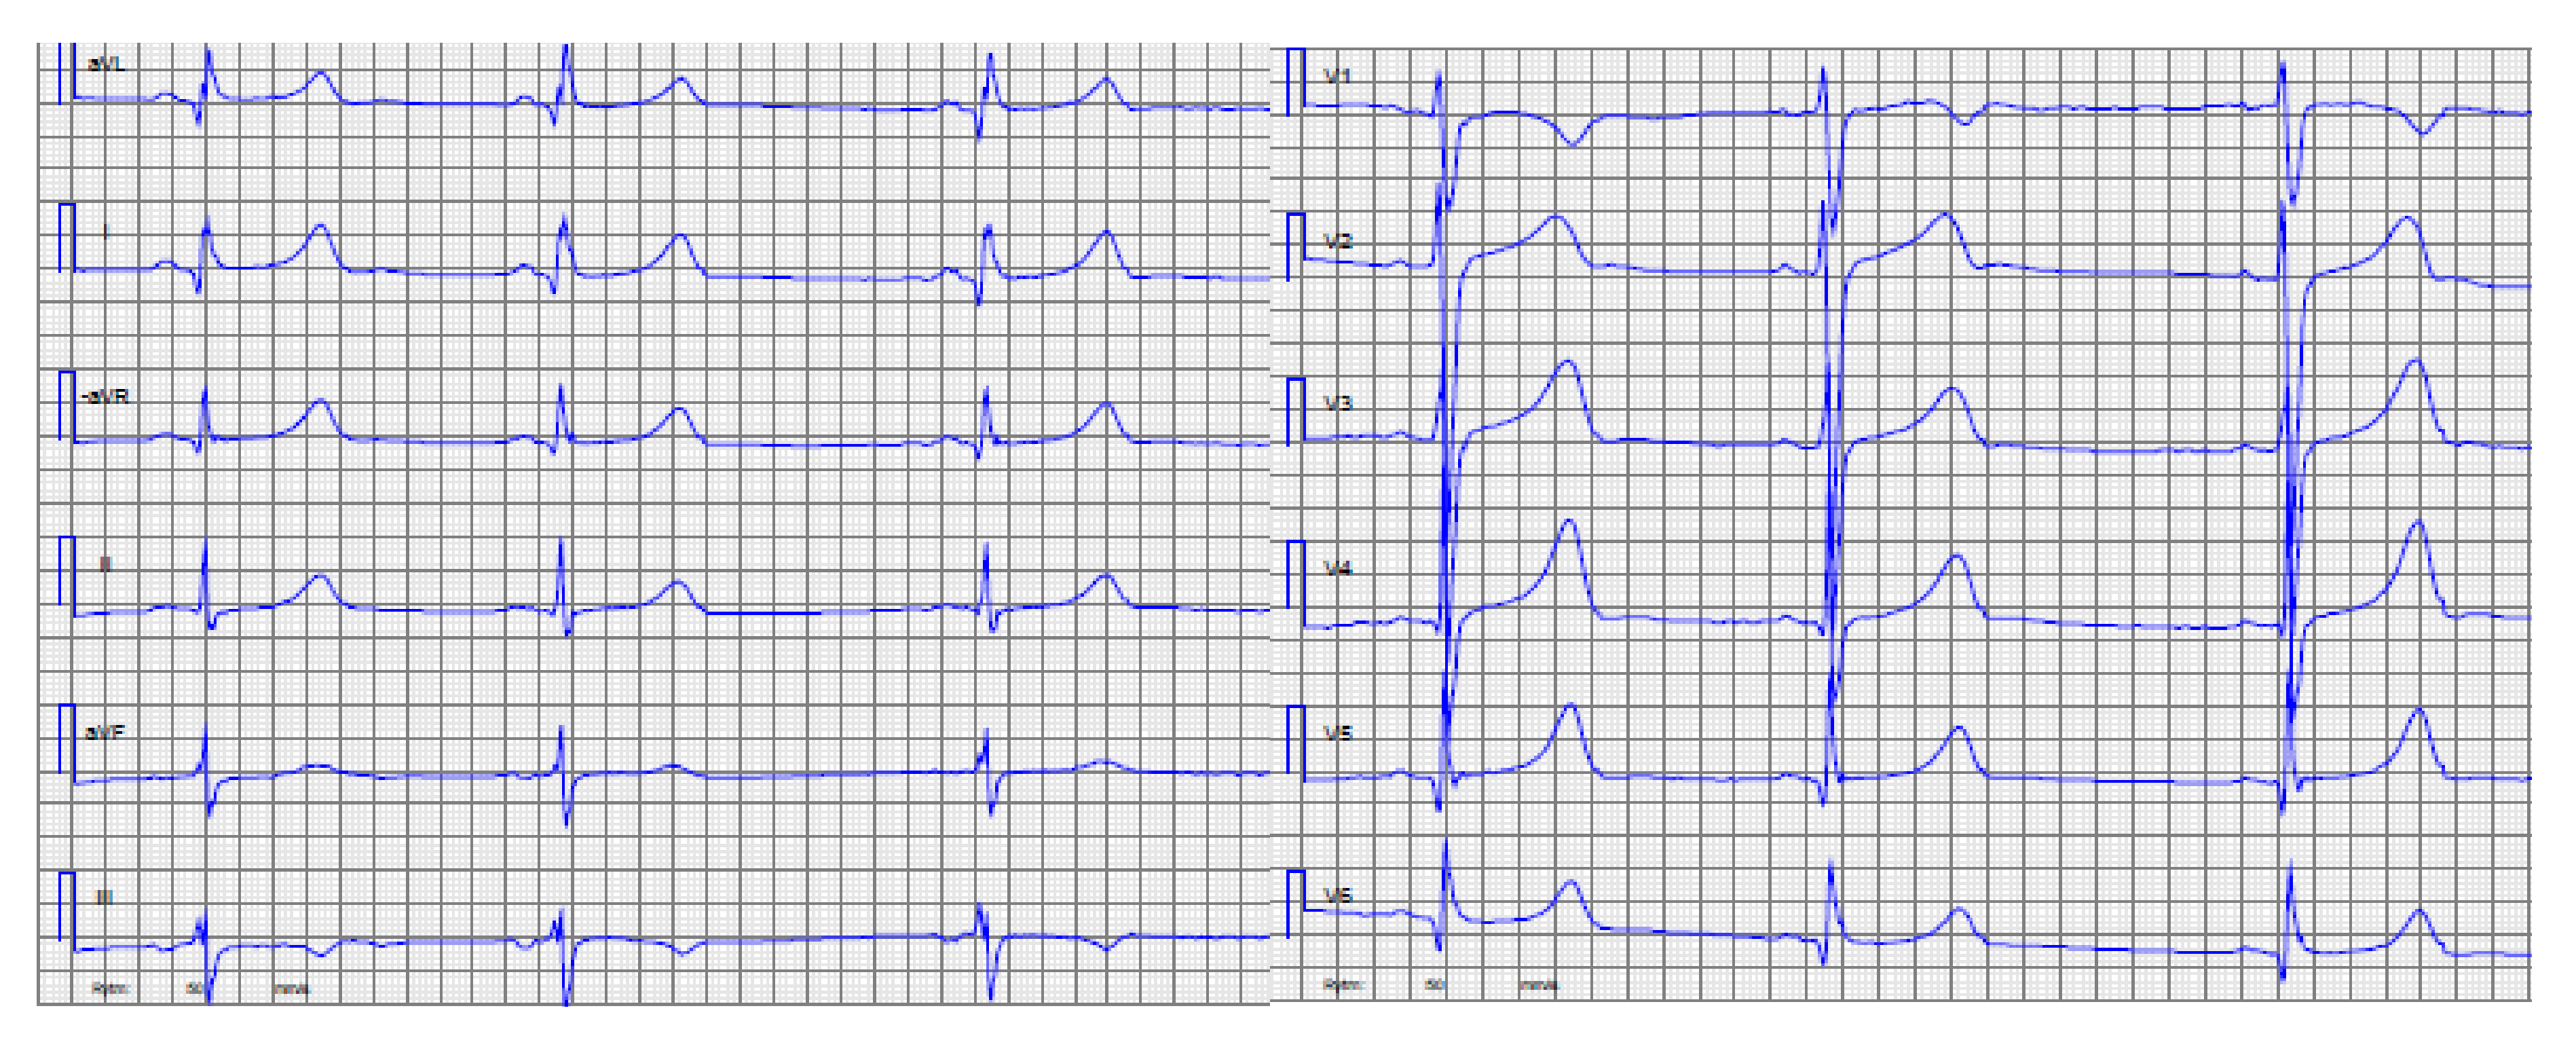

| 3. | II:1 | 14 | M | 0 | First symptom pro-longed QTc, rapid evolving to HCM ASH and LVNC. | 2 | 3 | Mother mVSD, LVNC | ABCC9 Chr12(GRCh37):g.21997457A>C, NM_005691.3:c.3275T>G p.I1092S | PP3 VUS/Yes |

| 4. | II:4 | 8 | M | 2 | ASH diastolic impairment | 6 | 9 | Sister, Father, Uncle with HCM, Uncle and grandfather SCD due to HCM | FLNC Chr7(GRCh37):g.128496973C>T, NM_001458.4:c.7559C>T, p.T2520I | PM2 VUS/Yes |